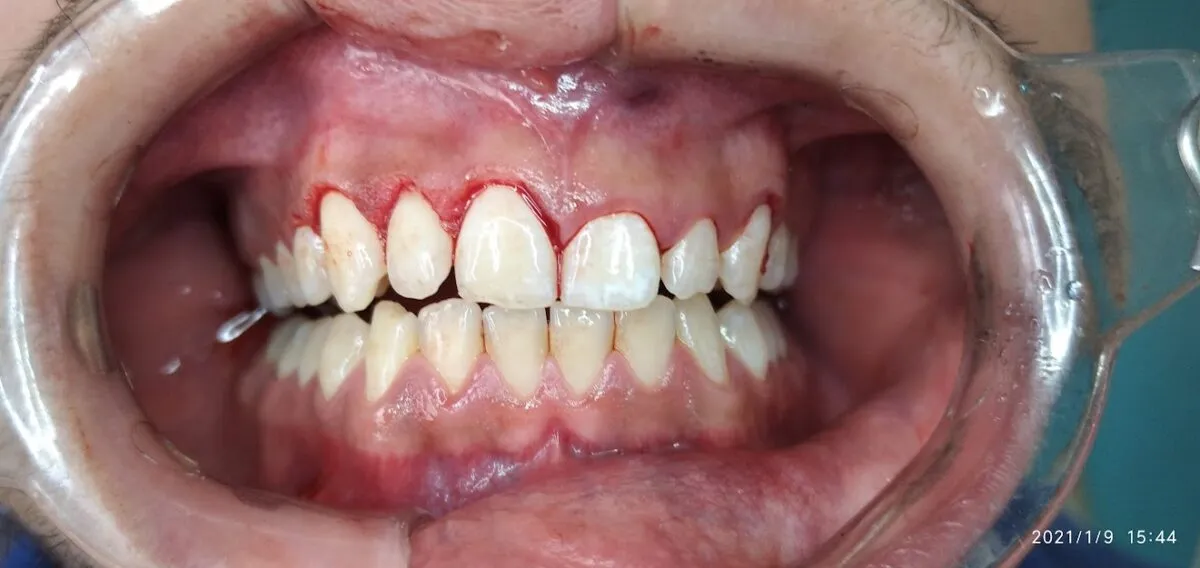

In this article we will show you a case of gingivectomy from before, during and after